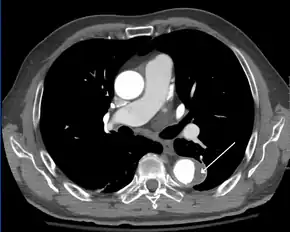

Computed tomography

Computed tomography angiography is a fast, noninvasive test that gives an accurate three-dimensional view of the aorta. These images are produced by taking rapid, thin-cut slices of the chest and abdomen, and combining them in the computer to create cross-sectional slices. To delineate the aorta to the accuracy necessary to make the proper diagnosis, an iodinated contrast material is injected into a peripheral vein. Contrast is injected and the scan performed using a bolus tracking method. This type of scan is timed to an injection to capture the contrast as it enters the aorta. The scan then follows the contrast as it flows through the vessel. It has a sensitivity of 96 to 100% and a specificity of 96 to 100%. Disadvantages include the need for iodinated contrast material and the inability to diagnose the site of the intimal tear.

- Aortic dissection

- CT with contrast demonstrating aneurysmal dilation and a dissection of the ascending aorta (type A Stanford)

- Chest CT with descending (type B Stanford) aortic dissection (red circle)

- Type A dissection with pericardial effusion as a result.